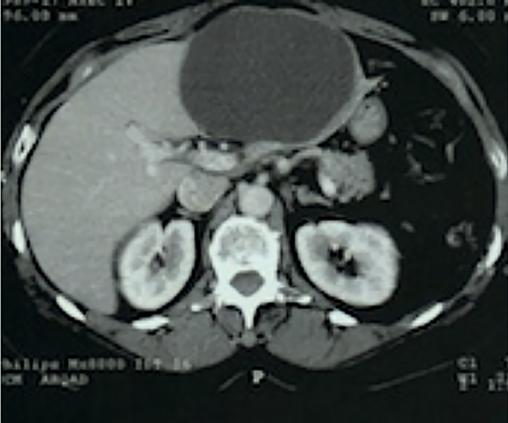

Cette masse augmentant rapidement, avec intensification des douleurs et apparition d’une gêne à l’inspiration, un scanner abdominal avec injection est demandé en urgence. Il confirme un volumineux kyste liquidien occupant tout le segment hépatique n° III (fig. 2 ).

Cette masse augmentant rapidement, avec intensification des douleurs et apparition d’une gêne à l’inspiration, un scanner abdominal avec injection est demandé en urgence. Il confirme un volumineux kyste liquidien occupant tout le segment hépatique n° III (

L’imagerie par résonance magnétique est recommandée en première intention pour la caractérisation des lésions problématiques. En urgence, le scanner abdominal a été plus facile à obtenir pour Marcelline.